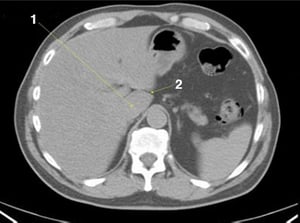

CT-Scan von Abdomen und Becken mit normaler Anatomie ohne Kontrastmittel (Folie 20)

1 = Aortenbifurkation

© Springer Science+Business Media